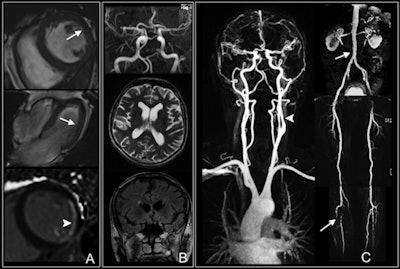

In the current study, the researchers enrolled 65 patients with type 1 or type 2 diabetes and a disease duration of at least 10 years. The patients underwent contrast-enhanced whole-body MRI exams, including brain, cardiac, and vascular sequences at baseline, between June 2005 and December 2006. Imaging was performed on either a 3- or 1.5-tesla system (Magnetom Tim Trio or Magnetom Avanto, Siemens Healthcare).

The prevalence of any findings at whole-body MRI was considered high (66%) by the authors. In addition, the prevalence of findings was similar between cardiovascular (36%), cerebrovascular (39%), and peripheral vessel imaging (43%).

Breaking down the results further, positive late gadolinium enhancement in any myocardial segment had the highest prevalence (28%) among cardiac findings, while an abnormal amount of white-matter lesions had the highest prevalence among cerebrovascular findings (23%).

The median time between whole-body MRI and the first major adverse cardiac and cerebrovascular event was 35 months, ranging from 10 to 58 months. The absence of any pathologic finding in diabetic patients was associated with a zero probably of a future event during follow-up. Furthermore, the presence of any detectable ischemic and/or atherosclerotic changes at whole-body MRI was associated with a MACCE rate of 20% at three years and 35% at six years.

As one might expect, patients who experienced a MACCE were more inclined to have abnormal cardiac, carotid, and peripheral vessel MRI results than those who had no adverse events.